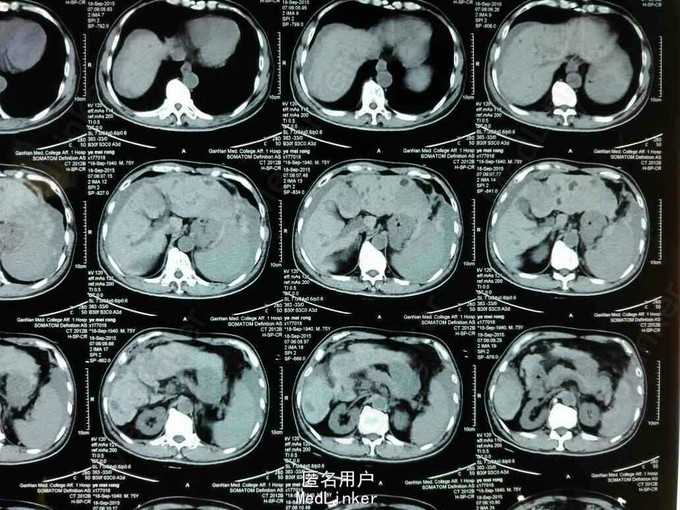

患者,男性,75岁,因“右上腹痛9小时”入院。既往有乙肝病毒肝炎病史,未予治疗。

查体:贫血貌,生命体征平稳,腹稍硬,可及压痛和反跳痛。辅查:肝脏弥漫性结节,考虑原发性肝癌,并破裂出血。AFP:1570ng/L。

诊断:原发性肝癌并破裂出血。治疗:给予补液,止血对症处理后,行TACE术。

随访:患者术后恢复好,已出院。讨论:该患者整个肝脏弥漫性癌肿,无手术指征,患者又合并肿瘤破裂出血,生命体征平稳,选择急诊行TACE术。